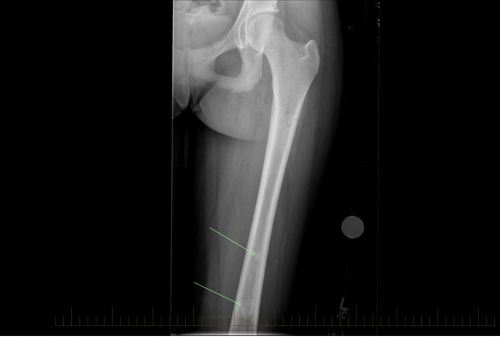

X-ray shows an anterior/posterior (front to back) view of skip lesions from osteosarcoma in a patient's femur.

X-rays are used to see if the cancer has spread to other parts of the bone.